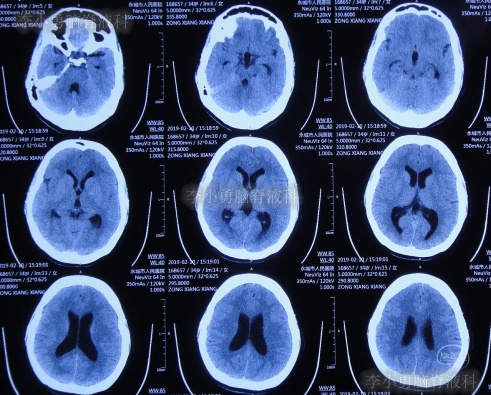

患者2019年2月初,因数次出现发作性黑蒙,2019年2月10日就诊于当地的河南省永城市某医院,查头颅CT未见明显异常(图-1);次日再查头颅核磁、颈椎核磁(图-2、图-3)后发现小脑扁桃体下疝畸形合并脊髓空洞。

图-1:2019年2月10日头颅CT